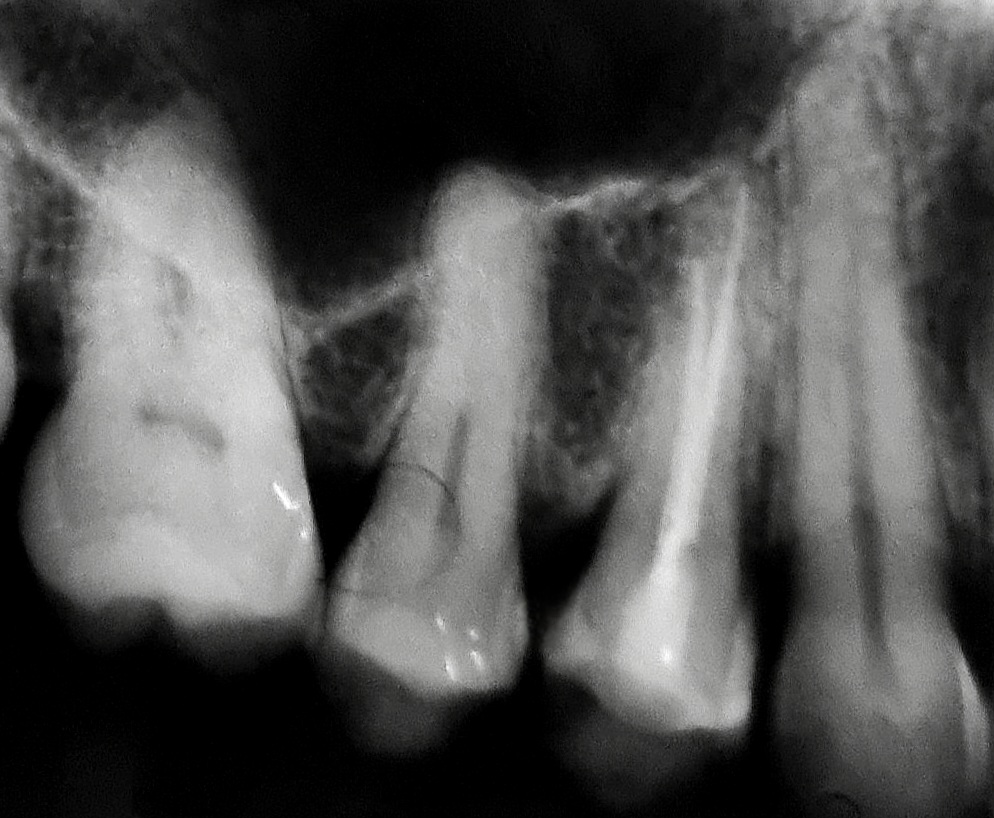

Molares com atresias e curvaturas, urgências endodônticas, dentes anteriores...

Remoção de elementos protéticos, retentores intra-radiculares (fibra de vidro e metálicos) e materiais obturadores.